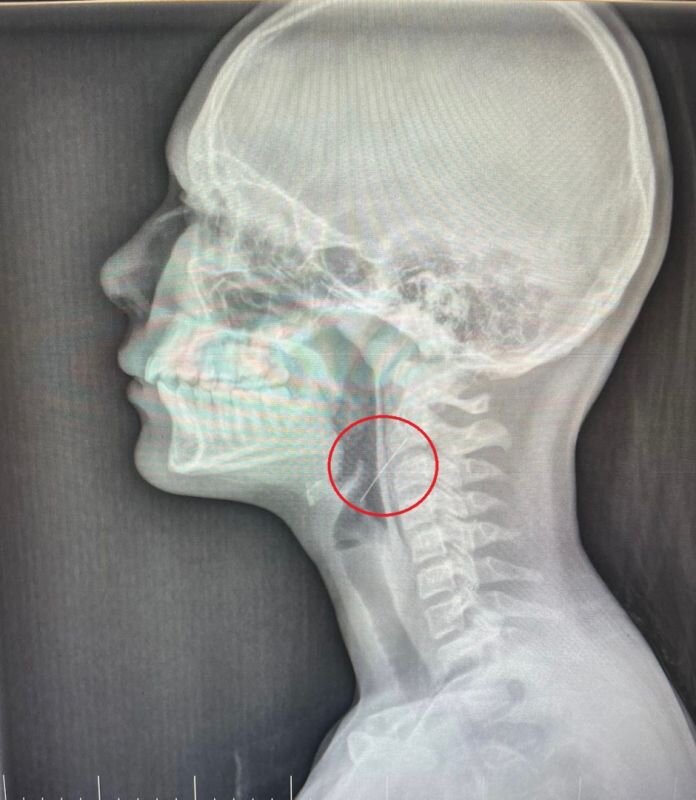

Девочка проглотила иголку, когда вешала гирлянду дома в Воронеже

Фото: Минздрав Воронежской области

Доктора оперировали ребёнка всю ночь. Они провели прямую ларингоскопию, в ходе которой обнаружили, что игла вонзилась в правую стенку глотки.